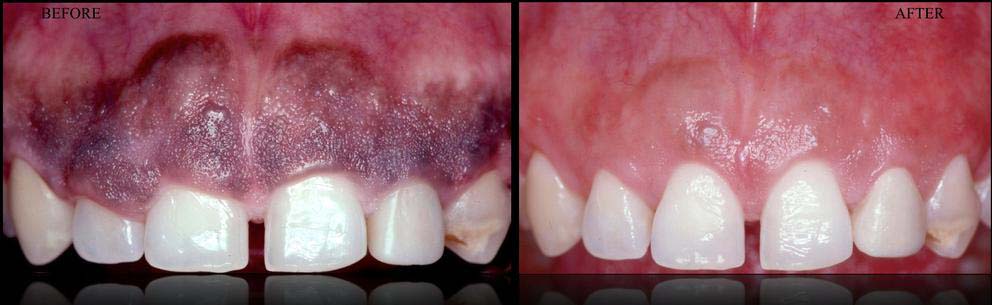

- ESTHETIC CROWN LENGTHENING ---> GUMMY SMILE CORRECTION